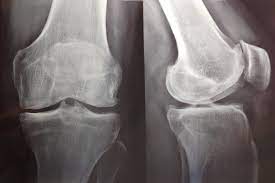

En este estudio poblacional, una tasa de pérdida de peso lenta a moderada, pero no rápida, inducida por medicamentos contra la obesidad se asocia con un menor riesgo de mortalidad por todas las causas en personas con sobrepeso u obesidad y artrosis de rodilla o cadera. Arthritis Rheumatol. 6 de diciembre de 2023